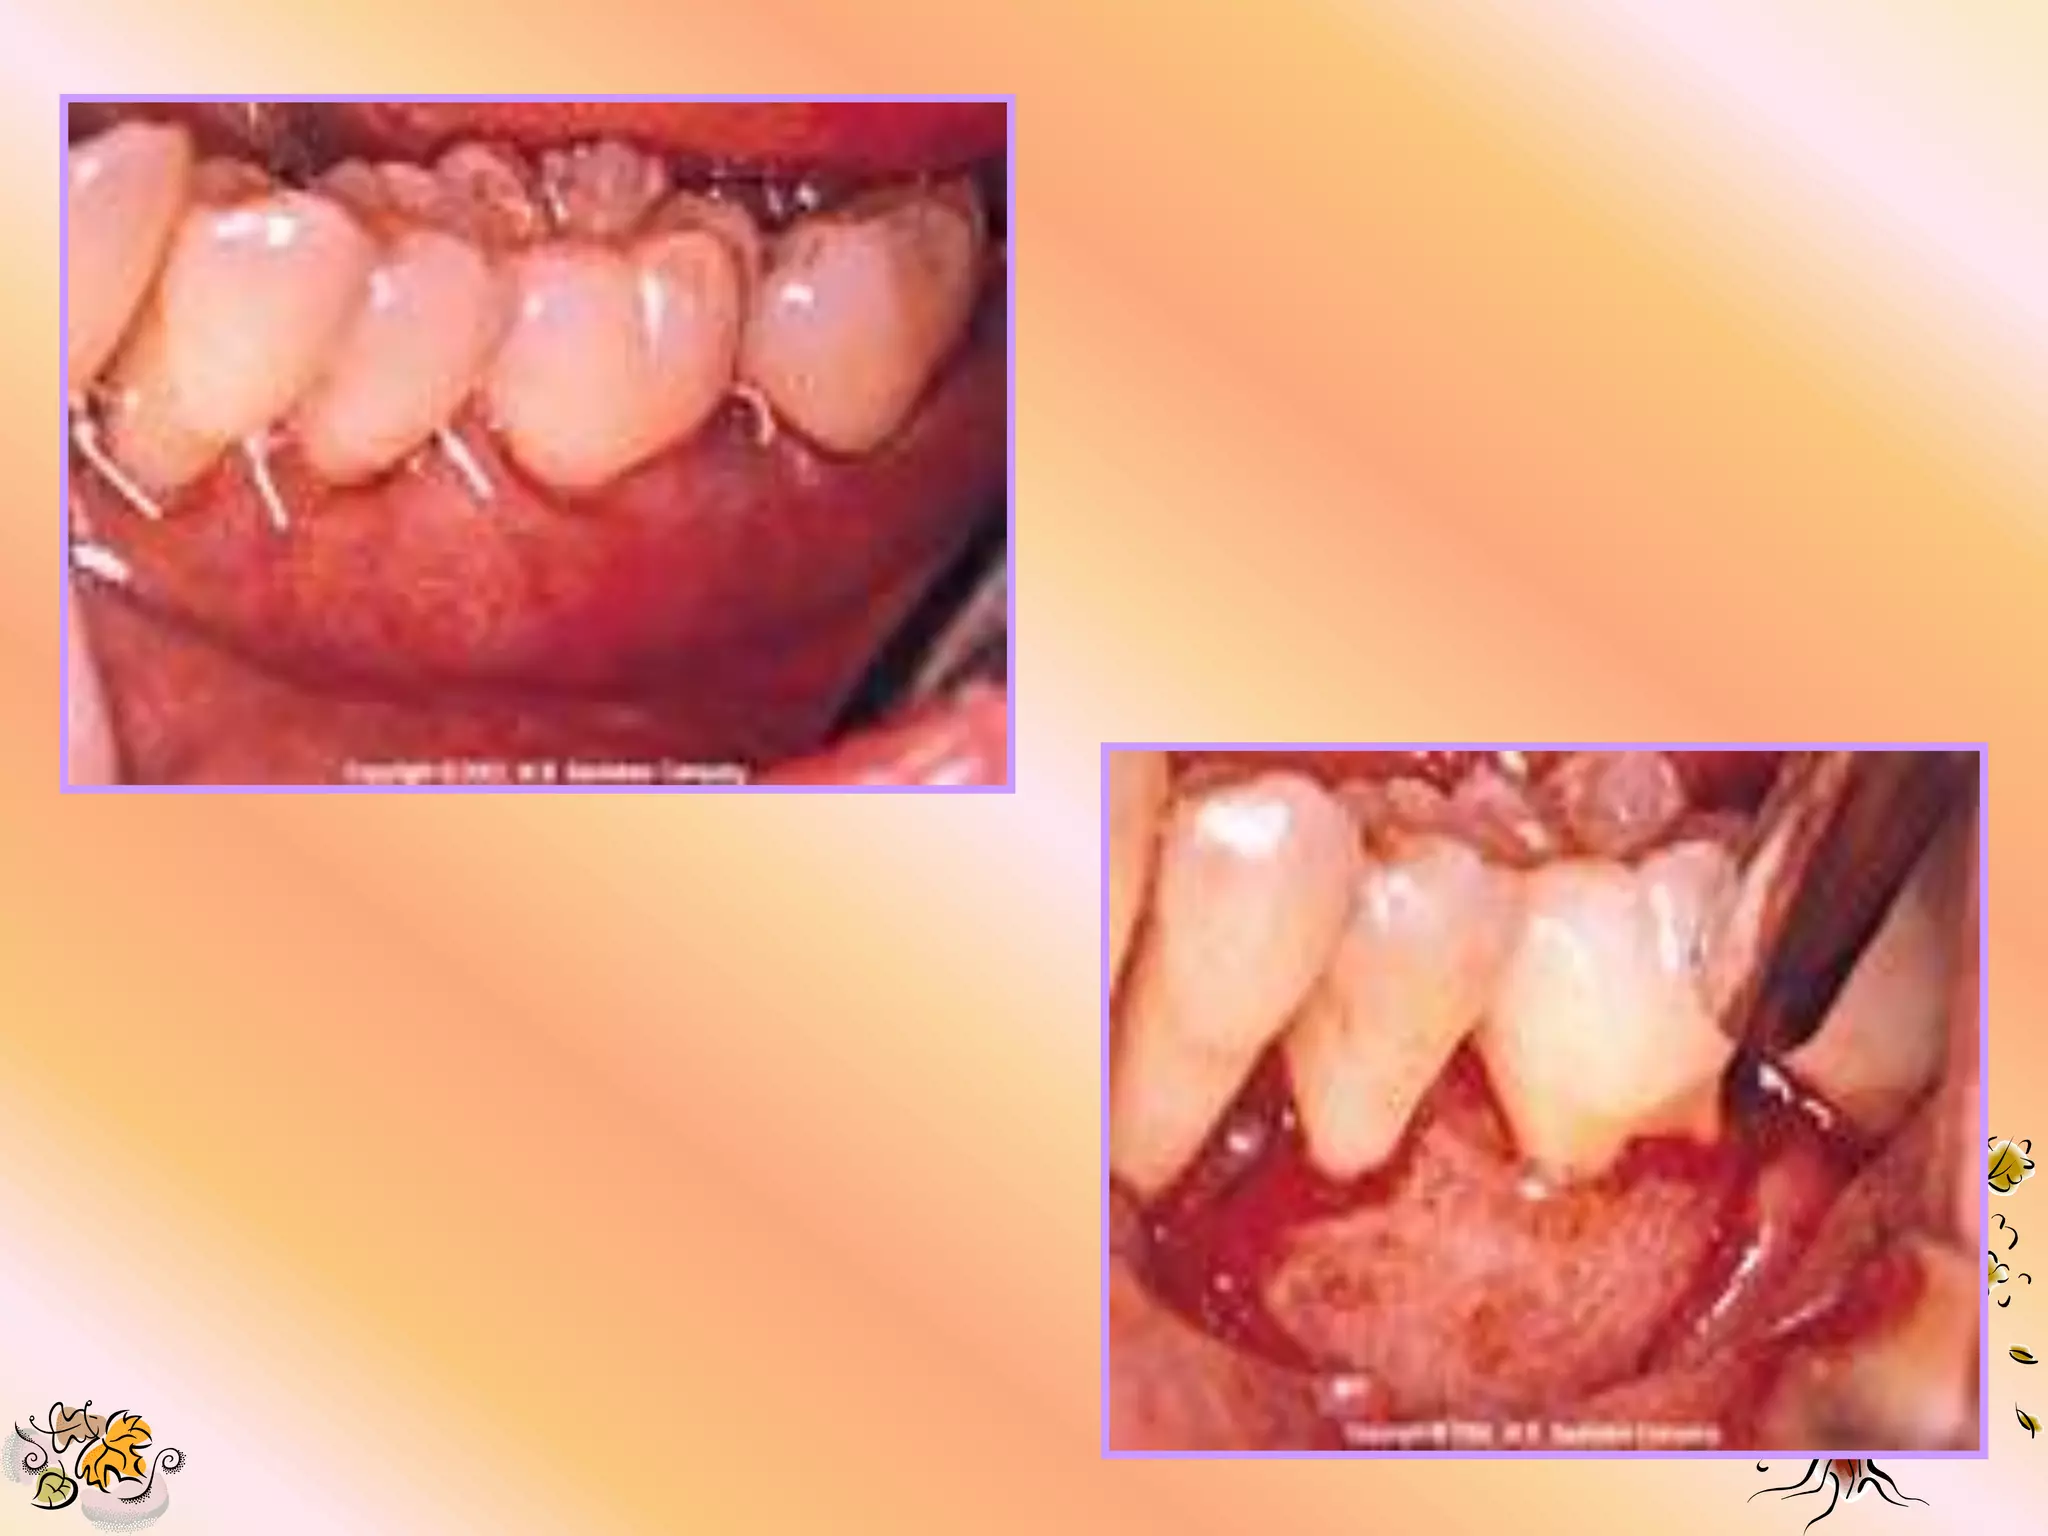

MATERIAL REMOVAL 1. Removalshould be 4 to 8 wks after placement or any time a serious complication occurs.

2. If thematerial can not be removed with a gentle tug, sharp dissection is recommended.

3. Extreme careshould be used to avoid damaging the underlying the new granulation tissue. 4. A small tissue forcep is used to remove the material. 5. The flap is re-approximated over the new tissue & sutured with silk suture.

1. Peridox mouth wash should be for 10 days if the material becomes exposed, peridox should be used untill removal. 2. Antibiotic coverage- (7-10 days) Tetracycline 250mg q.i.d. Doxycycline 100mg b.i.d. 3. Use of periodontal dressing is optional. 4. Flossing at the treatment site is to be avoided while the material is in place.

5. The patientshould be seen biweekly if there is no exposure, & wkly if exposure is present. 6. Do not attempt to cover the previously exposed material. 7. The material should be removed immediately if any complication develops.